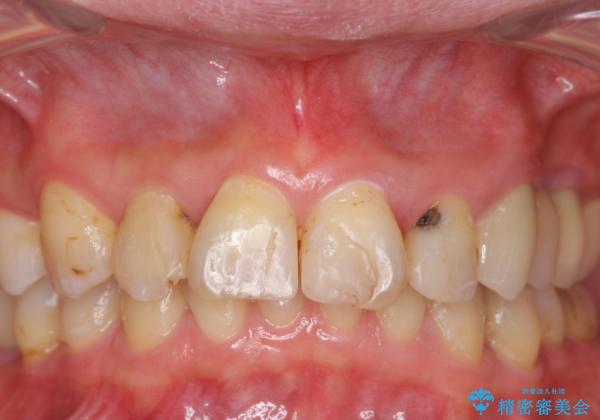

前歯の虫歯 つぎはぎの歯をセラミックに

- 矯正治療後に、前歯の樹脂の詰め物のやりかえを提案していましたが、治療は当時行いませんでした。

その後3年間来院がなく、その間に前歯の虫歯の進行があり、治療を行いました。

やはり、樹脂で虫食い状になってしまうと虫歯が進行しやすくなっているためクラウンがおすすめです。

下の前歯との距離(クリアランス)が大きくは取れなかったため、ジルコニアクラウンではなくe-maxクラウンにしました。

また、歯ぎしりでセラミックがかけるのを防ぐために、就寝時にはナイトガードを装着してもらっています。